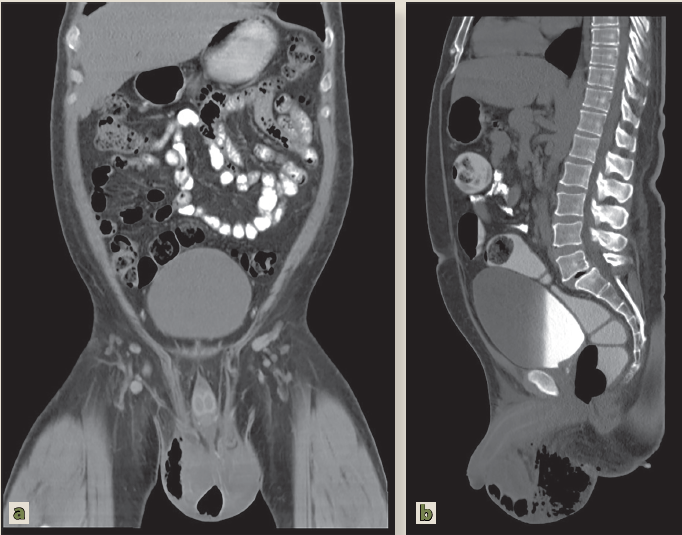

A la exploración física se encontró abdomen doloroso hipogastrio y fosas ilíacas, escroto edematoso, aumento de volumen escrotal, tejido necrótico en rafe escrotal con salida de material purulento (figura 2).

Imagen: Pérez Ladrón de Guevara et al.

Figura 2 a) Corte corona. b) Corte sartal de tomografía contrastada de abdomen en donde se visualiza el aumento de volumen escrotal, enfisema subcutáneo y colección líquida adyacentes, además de adenopatías inguinales. Datos compatibles con gangrena de Fournier

Se realizó tomografía computada (TC) en fase simple y contrastada de abdomen, donde se observó edema de tejidos blandos de la bolsa escrotal, ocupación de la misma por burbujas aéreas y colección líquida en su interior. Adenopatías mesentéricas, retroperitoneales e inguinales.